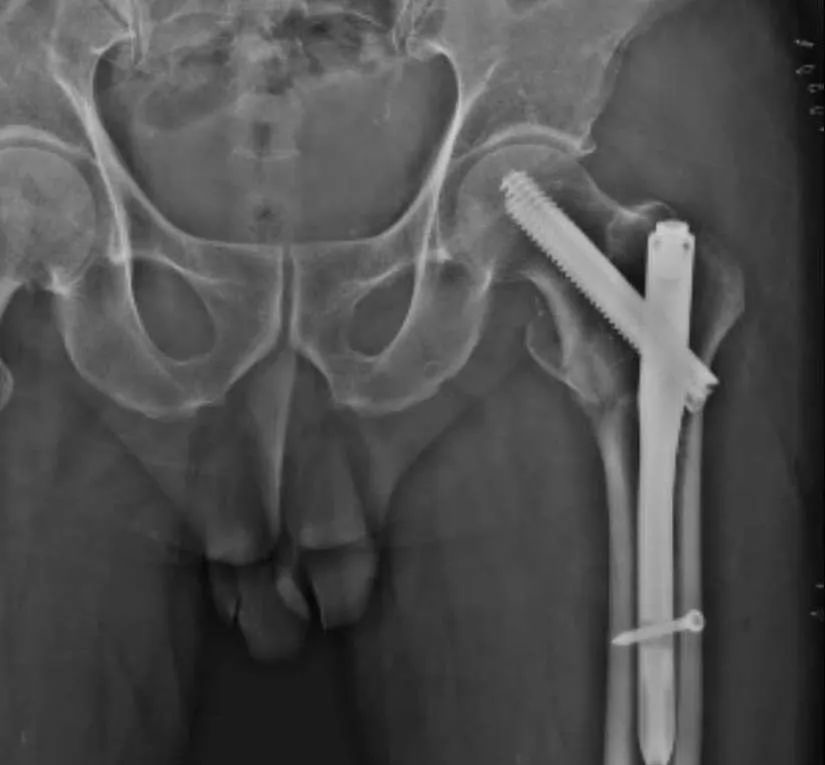

01什么是老年髋部骨折? 专家学者一致认为,髋部骨折临床比较常见,约占全身骨折的6.73%,约占股骨骨折的52.77%,包括股骨粗隆间骨折和股骨颈骨折。随着社会老龄化的不断加剧,老年髋部骨折的发生率在总体上也呈不断上升趋势,老年人往往不需要强大的外界力量,只需轻微跌摔或长时间劳动、负重即有可能发生骨折。髋部骨折好发于老年骨质疏松患者,女性多于男性,70岁以上骨折发病率明显增加。髋部骨折致残、致畸、死亡率高,是严重的骨科疾病。 股骨粗隆间骨折术前术后示意图

手术治疗老年股骨粗隆间骨折首选用髓内钉固定,手术治疗不但可以使老年股骨粗隆间骨折患者早期恢复关节功能和活动能力,也可降低骨折病的发生率和病死率,提高生活质量。换句话说就是随着医疗技术的提高,对于股骨粗隆间骨折手术创伤越来越小,术后恢复越来越快。

髓内钉内固定装置示意图 老年股骨颈骨折的主要手术治疗方式为人工股骨头置换和全髋关节置换。